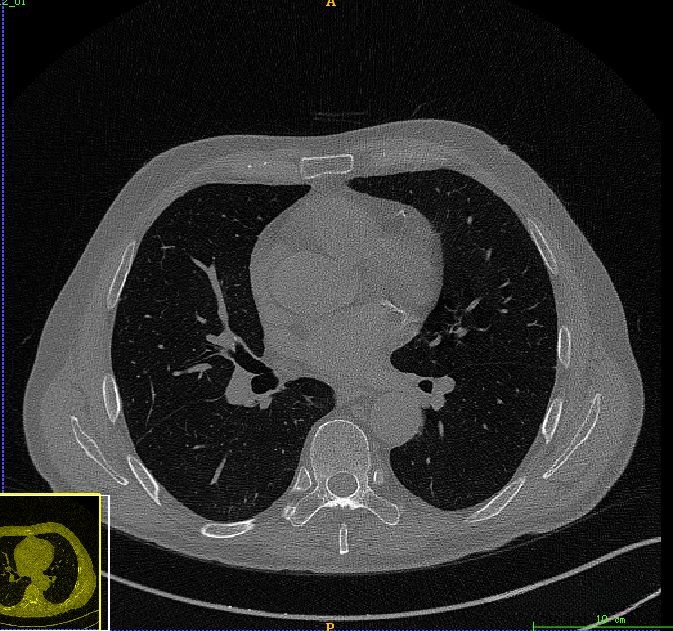

在本案例中,我们可以直接调用挑战赛提供的Mask来省略这一步骤的处理。而在本案例中,则对之前的医学图像处理案例(一)——基于CT图像的肺分割进行了深入分析与拓展研究,在这一过程中主要包含了六项关键步骤:首先,在观察图像时会发现存在一定的噪声干扰,并通过应用中值滤波器来去除这些噪声影响;其次,在进行图像分割时采用了大津阈值法作为主要手段;第三步则是对背景目标进行识别并予以剔除;第四步则重点进行了对噪声信息的尽量去除;第五步是对肺部轮廓边缘进行重构;第六步则最终实现了肺部组织区域的提取与确定。

在原始CT图像上观察到存在明显的噪声干扰,在后续的肺部分割过程中可能会受到一定影响为此处采用了中值滤波方法来进行预处理经过中值滤波处理后图像中的噪声得到了有效的抑制值得注意的是在此过程中血管信息也会被一定程度地抑制但这并不影响整体效果这一预处理步骤的主要目的是为了获得较为完整的肺部区域信息

最后得到肺部区域图像如下所示。